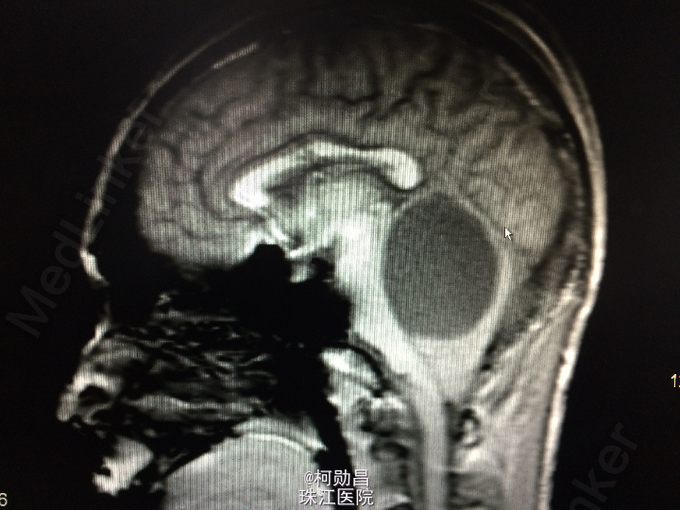

患者17岁男性,因“发现后颅窝占位1周”入院, 于1月前无明显诱因出现头晕、头痛,伴呕吐、肢体抽搐及行走不稳,无肢体乏力、意识障碍、视物模糊等,间至当地医院治疗,症状可缓解,1周前出现上述症状加重,遂至当地医院治疗,行头颅CT提示:后颅窝占位、梗阻性脑积水。后入我院,行手术治疗。病理结果提示:血管母细胞瘤